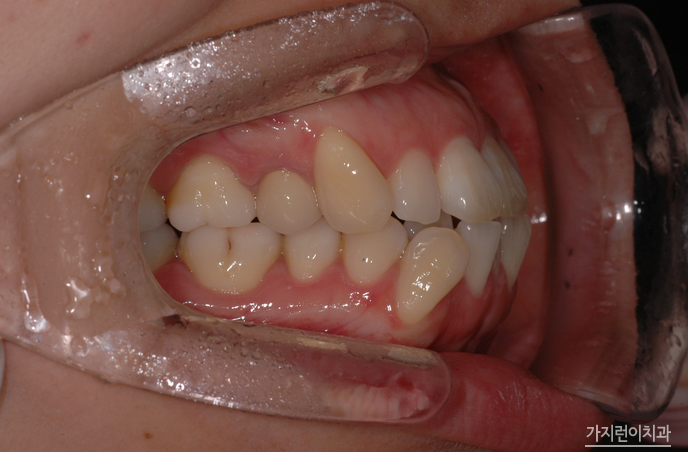

해당 환자의 경우 치아 문제에만 국한되어있는 게 아니라 골격적인 문제가 동반된 케이스였습니다. 때문에 안정적인 결과를 얻기 위해서 수술교정을 진행하게 되었는데요. 돌출입 양상을 보면 치아가 문제가 아닌 골격적인 문제인것을 확인해볼 수 있었습니다. 이런 케이스를 무리하게 비수술로 진행하게 되면 앞니가 들어간 옥니가 될 수 있겠는데요. 환자의 구강골격을 확인한 후에 수술교정으로 플랜을 수립해 진행한 결과 안정적인 결과를 얻을 수 있었습니다.

돌출입의 경우 순측으로 진행하게 될 경우 장치로 인해 교정 도중 입이 더 튀어나와보이는 양상이 생겨날 수 있었는데요. 교정 기간 동안 스트레스 받이 교정을 하기 위해 설측으로 진행하려는 분들이 많습니다. 환자분 역시 골격부분을 삭제하는 수술 후에 설측교정방식을 채택해주셨는데요. 일반적인 설측교정과 달리 특허를 받은 장치기 때문에 2개의 와이어를 사용해 안정적인 교정힘을 줄 수 있었습니다. 그렇다면 교정 후의 모습은 어떨까요?